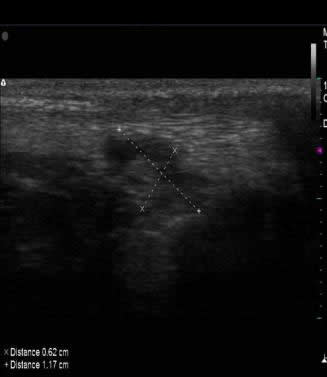

1) Ultrasonografía musculoesquelética inicial: Fotos 1 A y B. Imágenes corte longitudinal de bolsa sinovial.

(C) Imagen del tendón del músculo tríceps braquial, corte longitudinal con pérdida del patrón fibrilar.